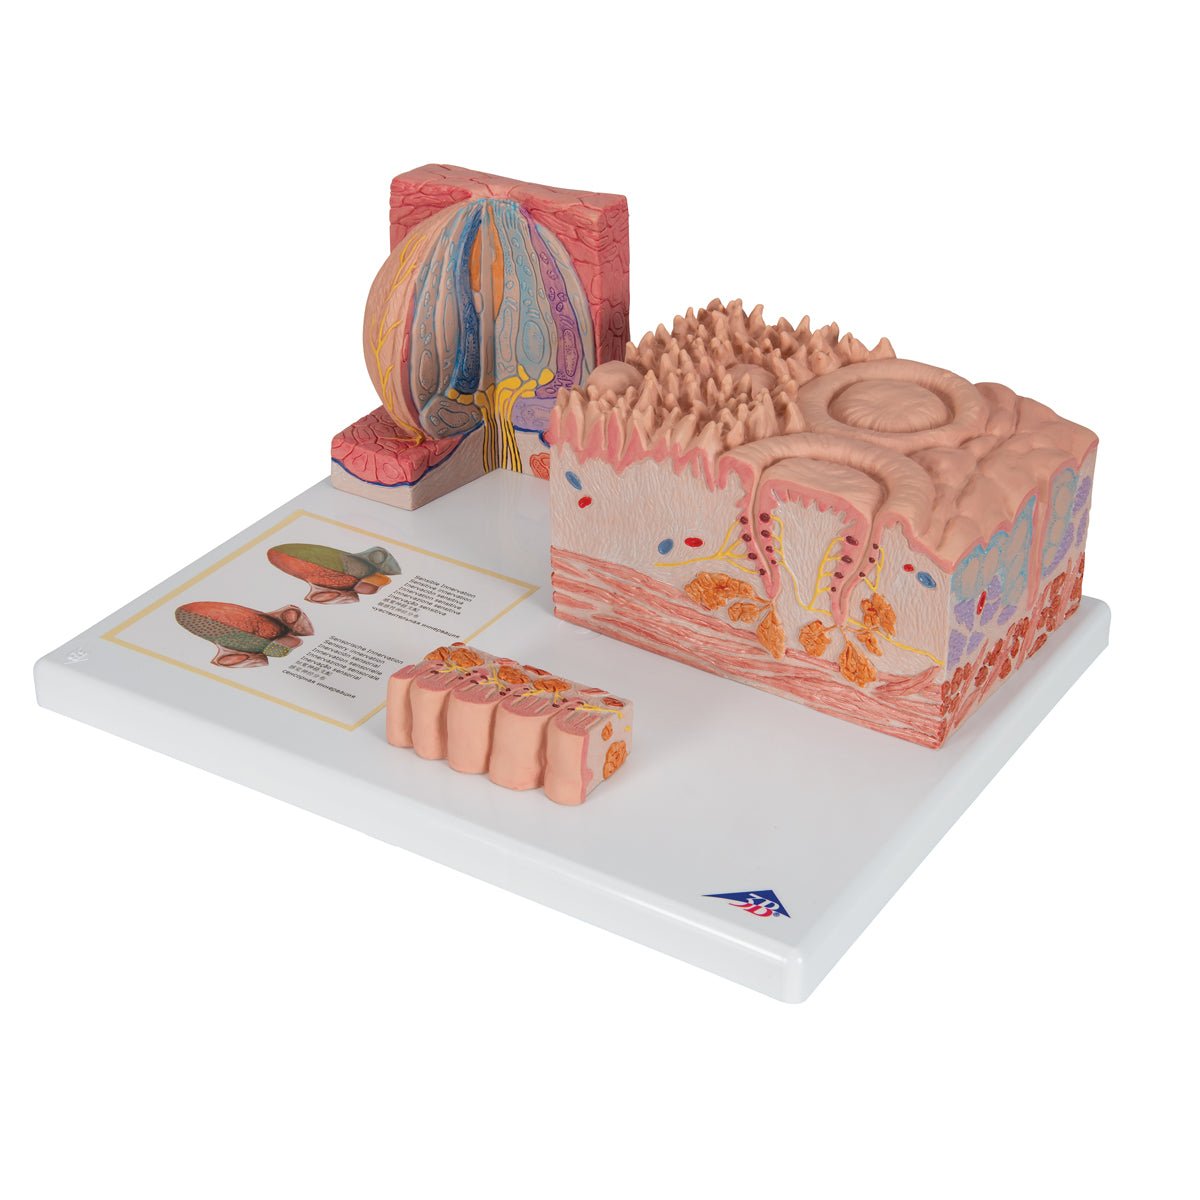

Salg af anatomiske modeller er det bærende element i eAnatomi, selvom vi også bruger mange ressourcer på at udvikle vores egne anatomiske materialer som fx plakater. Anatomiske modeller anvendes til forskellige formål og kan både vise afgrænset væv, organer samt organsystemer. Søger du en simpel model af knoglevæv eller måske en avanceret torso-model baseret på MRI teknologi, kan du finde det hele på eanatomi.com.